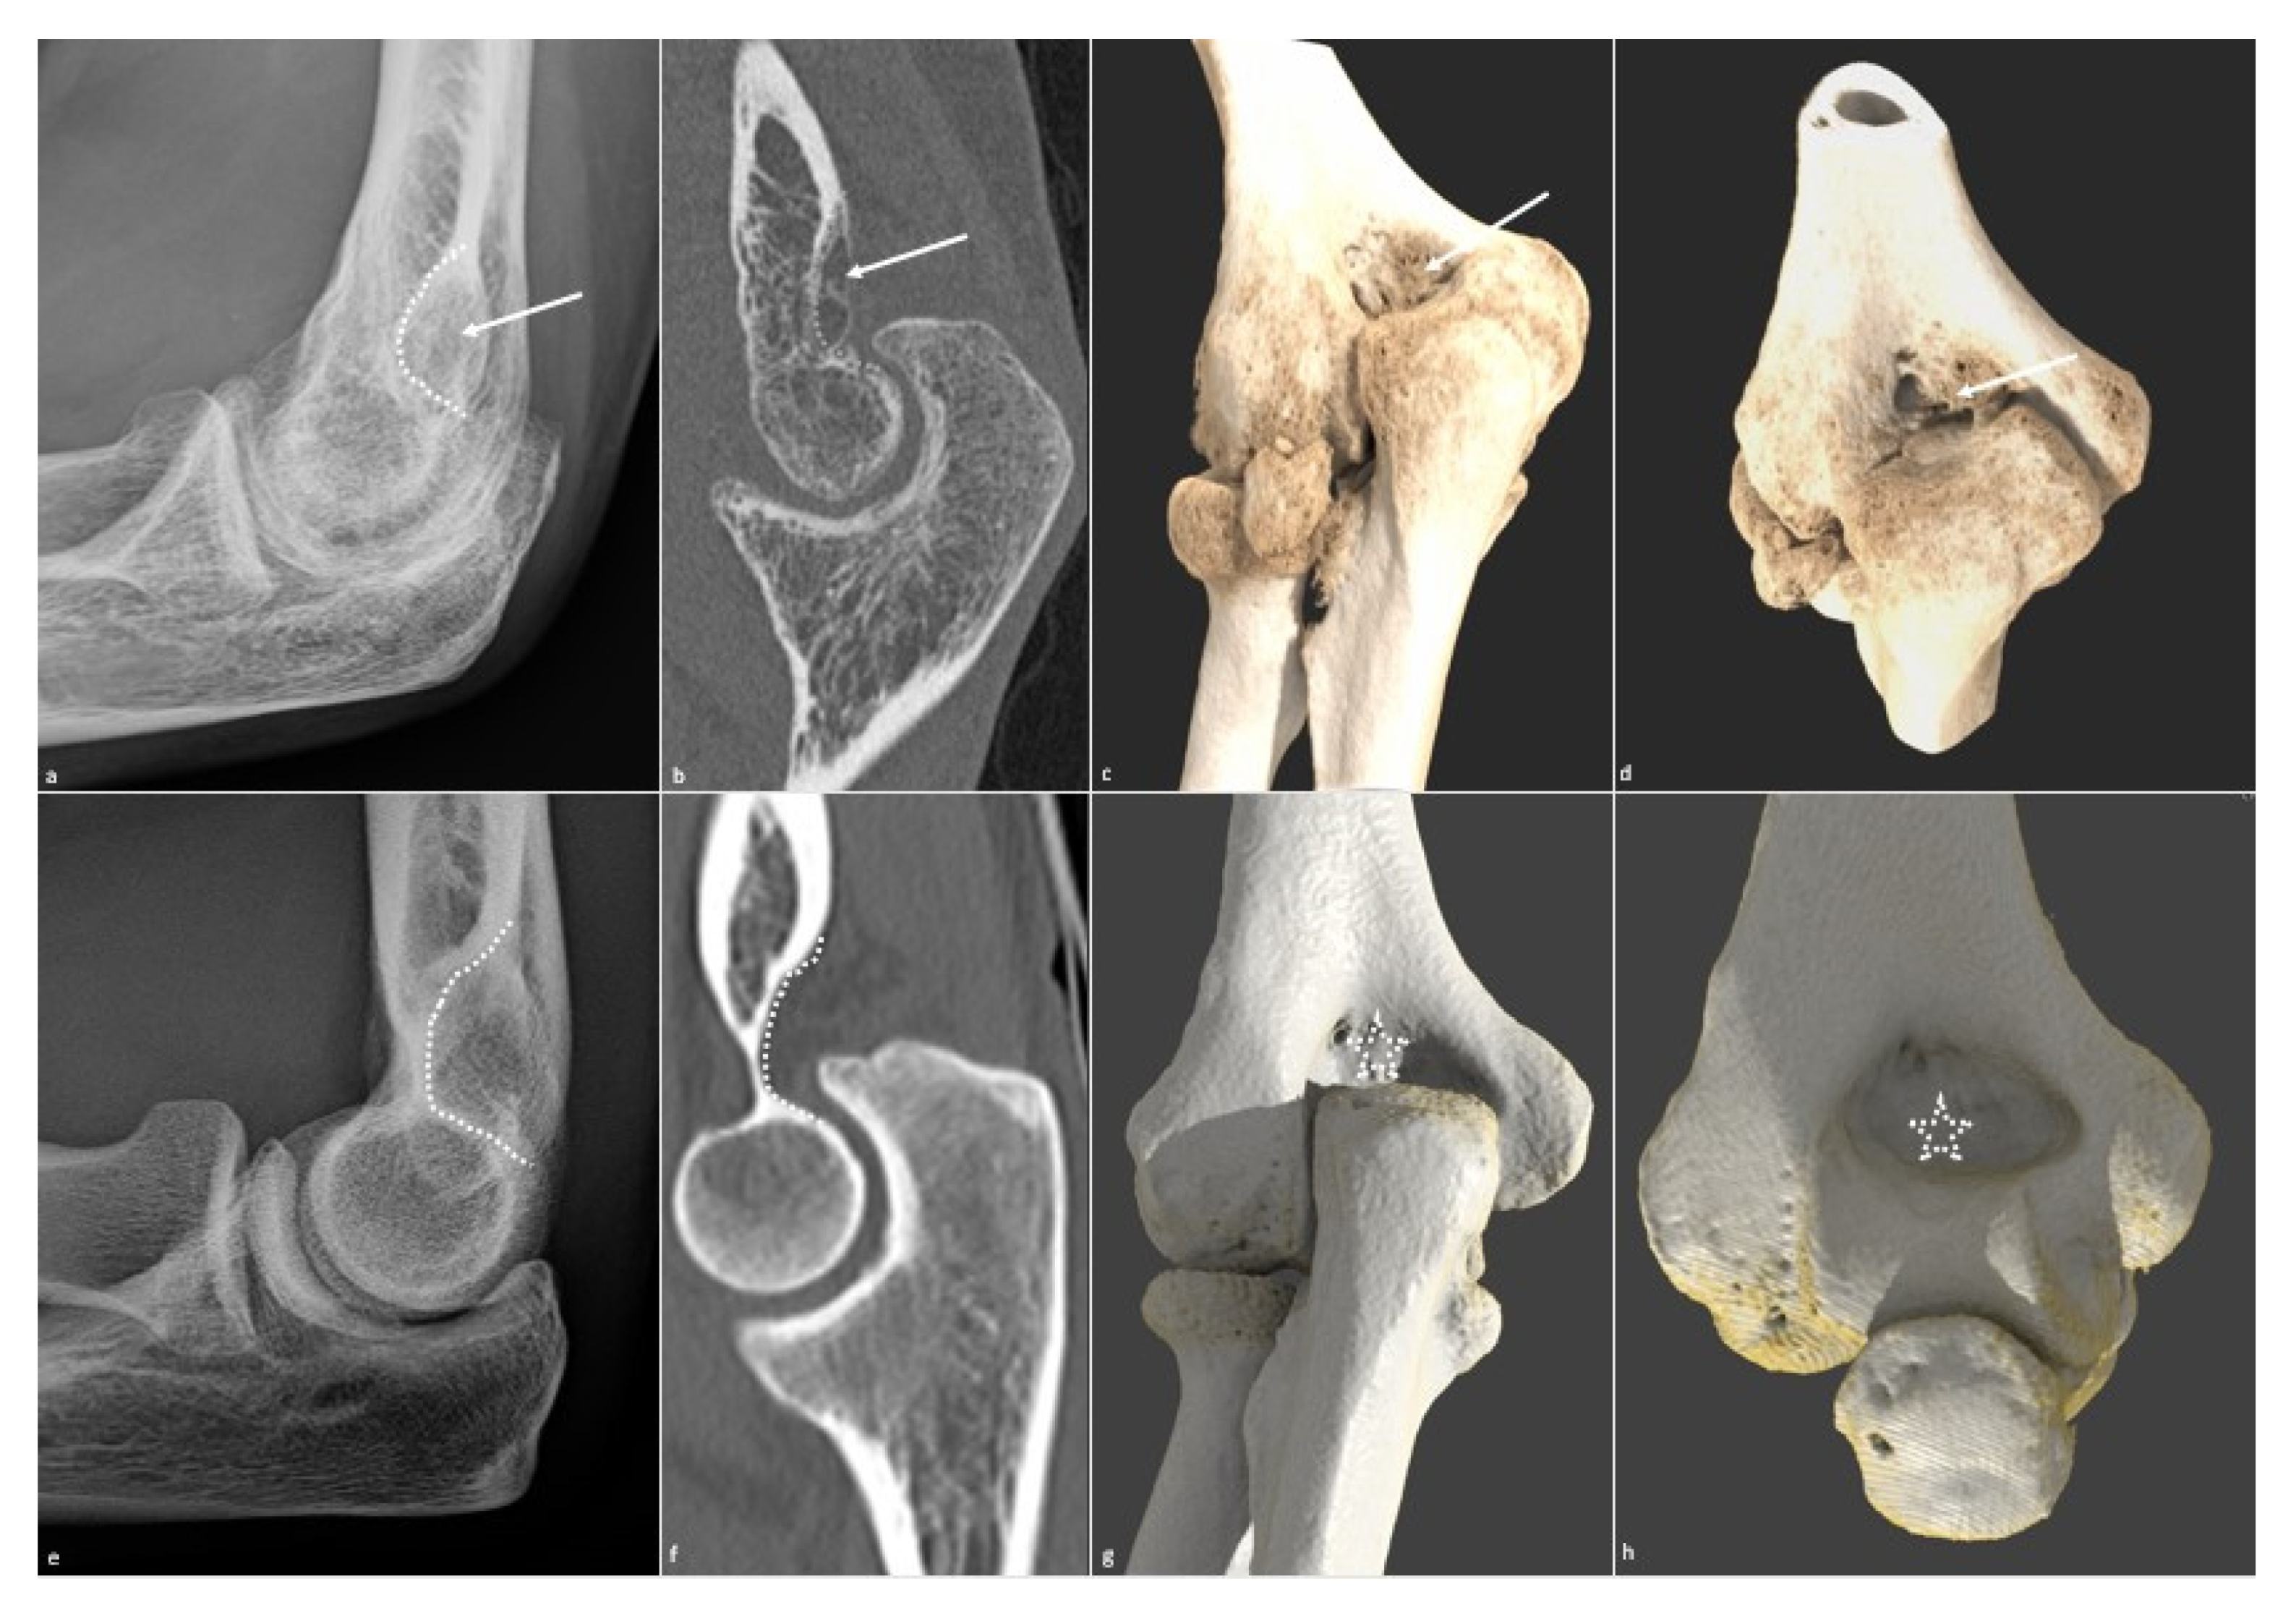

5.1. Conventional Radiographs

5.3. CT and CT Arthrography

5.4. MR Imaging

5.5. Dynamic and Kinematic CT